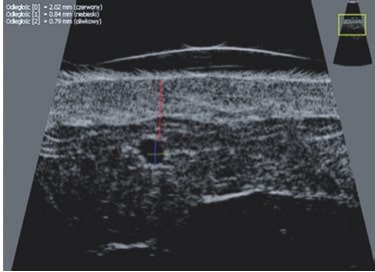

La ecografía Doppler permite obtener imágenes de grandes vasos y perforantes que suelen estar situados en las capas más profundas del tejido subcutáneo (fig. 1). Desgraciadamente, la ecografía convencional no es capaz de obtener imágenes de vasos más pequeños. Para visualizar los vasos más pequeños situados cerca de la superficie de la epidermis y en la capa superior del tejido subcutáneo, se utiliza el HFU (fig. 1). Gracias al uso de transductores con frecuencias superiores a 20 MHz, se obtiene una imagen ecográfica de alta resolución en la que podemos diferenciar estructuras menores de 0,1 mm. Sin embargo, cuanto mayor es la resolución, menor es la penetración del haz de ultrasonidos en las capas de la piel. Por lo tanto, dependiendo del transductor y del aparato, es posible penetrar en la piel hasta una profundidad de 20-30 mm como máximo. Tal penetración, junto con la alta resolución de la imagen, permite la evaluación incluso de vasos sanguíneos muy pequeños (fig. 2). Durante el examen con el uso de transductores de alta frecuencia, se puede evaluar con precisión el curso y la ubicación de los pequeños vasos en la piel. Esto es particularmente relevante para la selección del método de cierre del vaso y la planificación del procedimiento ya que, en la práctica, la superficie de la piel muestra muy a menudo únicamente un pequeño número de vasos o un ligero fragmento de un vaso; solo tras el examen por ecografía podemos determinar su número y curso reales. Para un cierre eficaz del vaso, es necesario hacerlo en toda su longitud. No debe limitarse al fragmento visto «a simple vista» en la superficie de la piel, ya que el cierre del fragmento causará su rápida recanalización(7). Con frecuencia, el vaso visible en la superficie de la piel cambia su curso, se vuelve más tortuoso y se desplaza a las capas más profundas de la piel(8). Por lo tanto, el curso de la vena y las perforantes deben conocerse y determinarse bien antes del procedimiento. El HFU también permite obtener imágenes de las perforantes entre pequeños vasos. Además, aparte de la evaluación del curso y la anatomía, la imagen ecográfica, gracias al software de ultrasonidos, también permite determinar los parámetros básicos como el diámetro del vaso, el grosor de su pared, la profundidad en la piel así como la presencia o ausencia de perfusión en el interior del vaso(6) (fig. 3). Gracias al transductor electrónico multielemento con la frecuencia de 40 MHz introducido en el mercado por Ultrasonix, también es posible visualizar la perfusión en los vasos en el modo Doppler color (fig. 4).